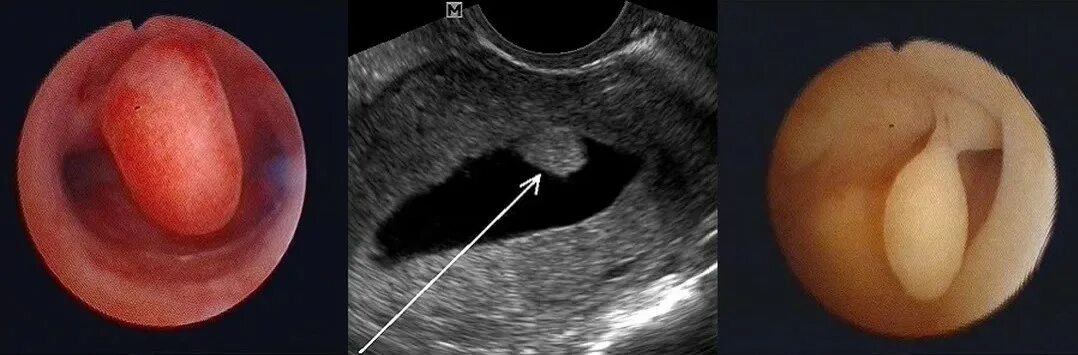

Полип эндометрия в матке причины